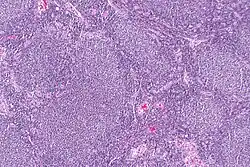

![]() | Dysgerminoma | Dysgerminoma characterized by uniform cells resembling primordial germ cells separated by fibrous septa with lymphocytes. | Category: Histopathology of ovarian dysgerminoma | Ovarian dysgerminoma |